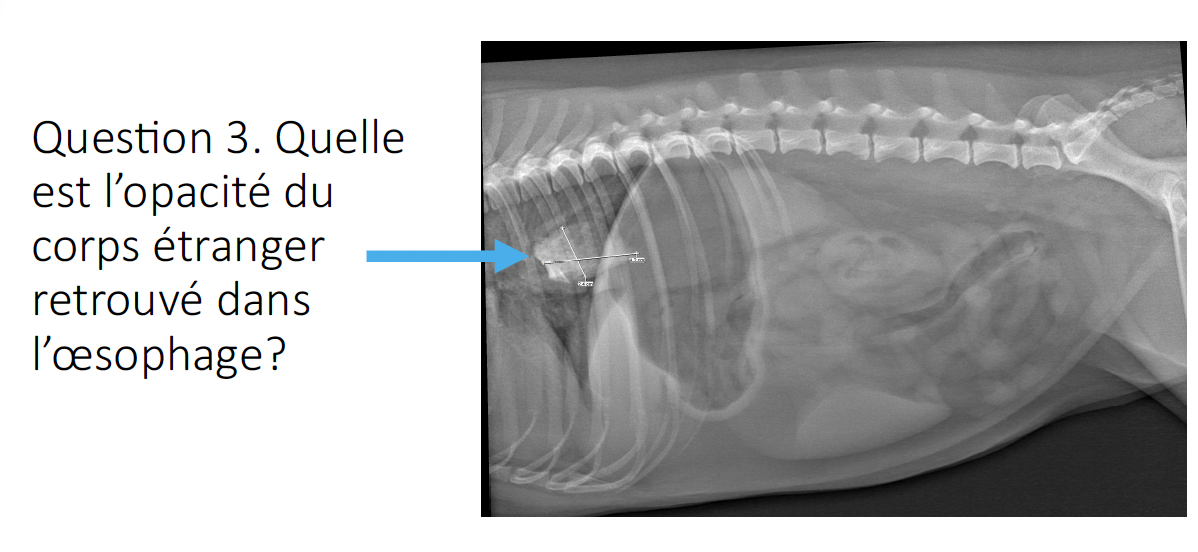

3

Q

a) adipeuse

b) tissus mous

c) liquidienne

d) métallique

e) minérale

A

*attention liquidienne et tissus mous correspondent à la même opacité